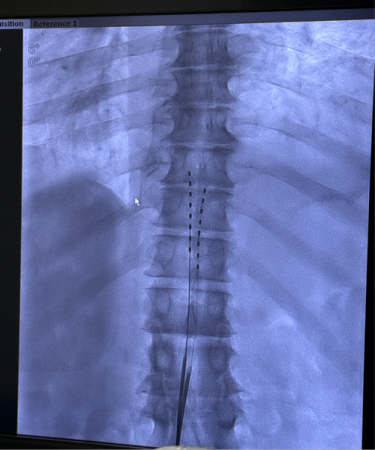

The surgery was performed under DSA

(Digital Subtraction Angiography) guidance. Under the direction of Chief

Physician Xiao Hong, the surgical team, consisting of Nurse Yin Yan and

Research Assistant Lu Fan, precisely delivered the electrode to the corresponding

segment of the patient's epidural space and completed intraoperative

stimulation parameter adjustments. Mr. T immediately reported that the coverage

area of the electrical stimulation highly coincided with his pain region,

experiencing an immediate analgesic effect. The surgical procedure was

completed smoothly.

Electrode Successfully Implanted